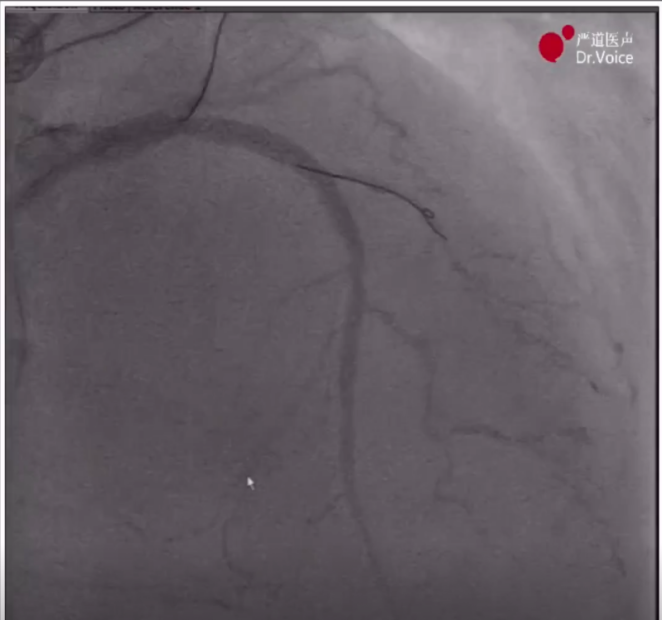

1、术前造影显示LAD近中段弥漫病变,LCX中段完全闭塞,RCA近段完全闭塞、远端形成侧枝循环。

LAD、LCX造影结果

RCA远端侧枝循环

RCA近端完全闭塞